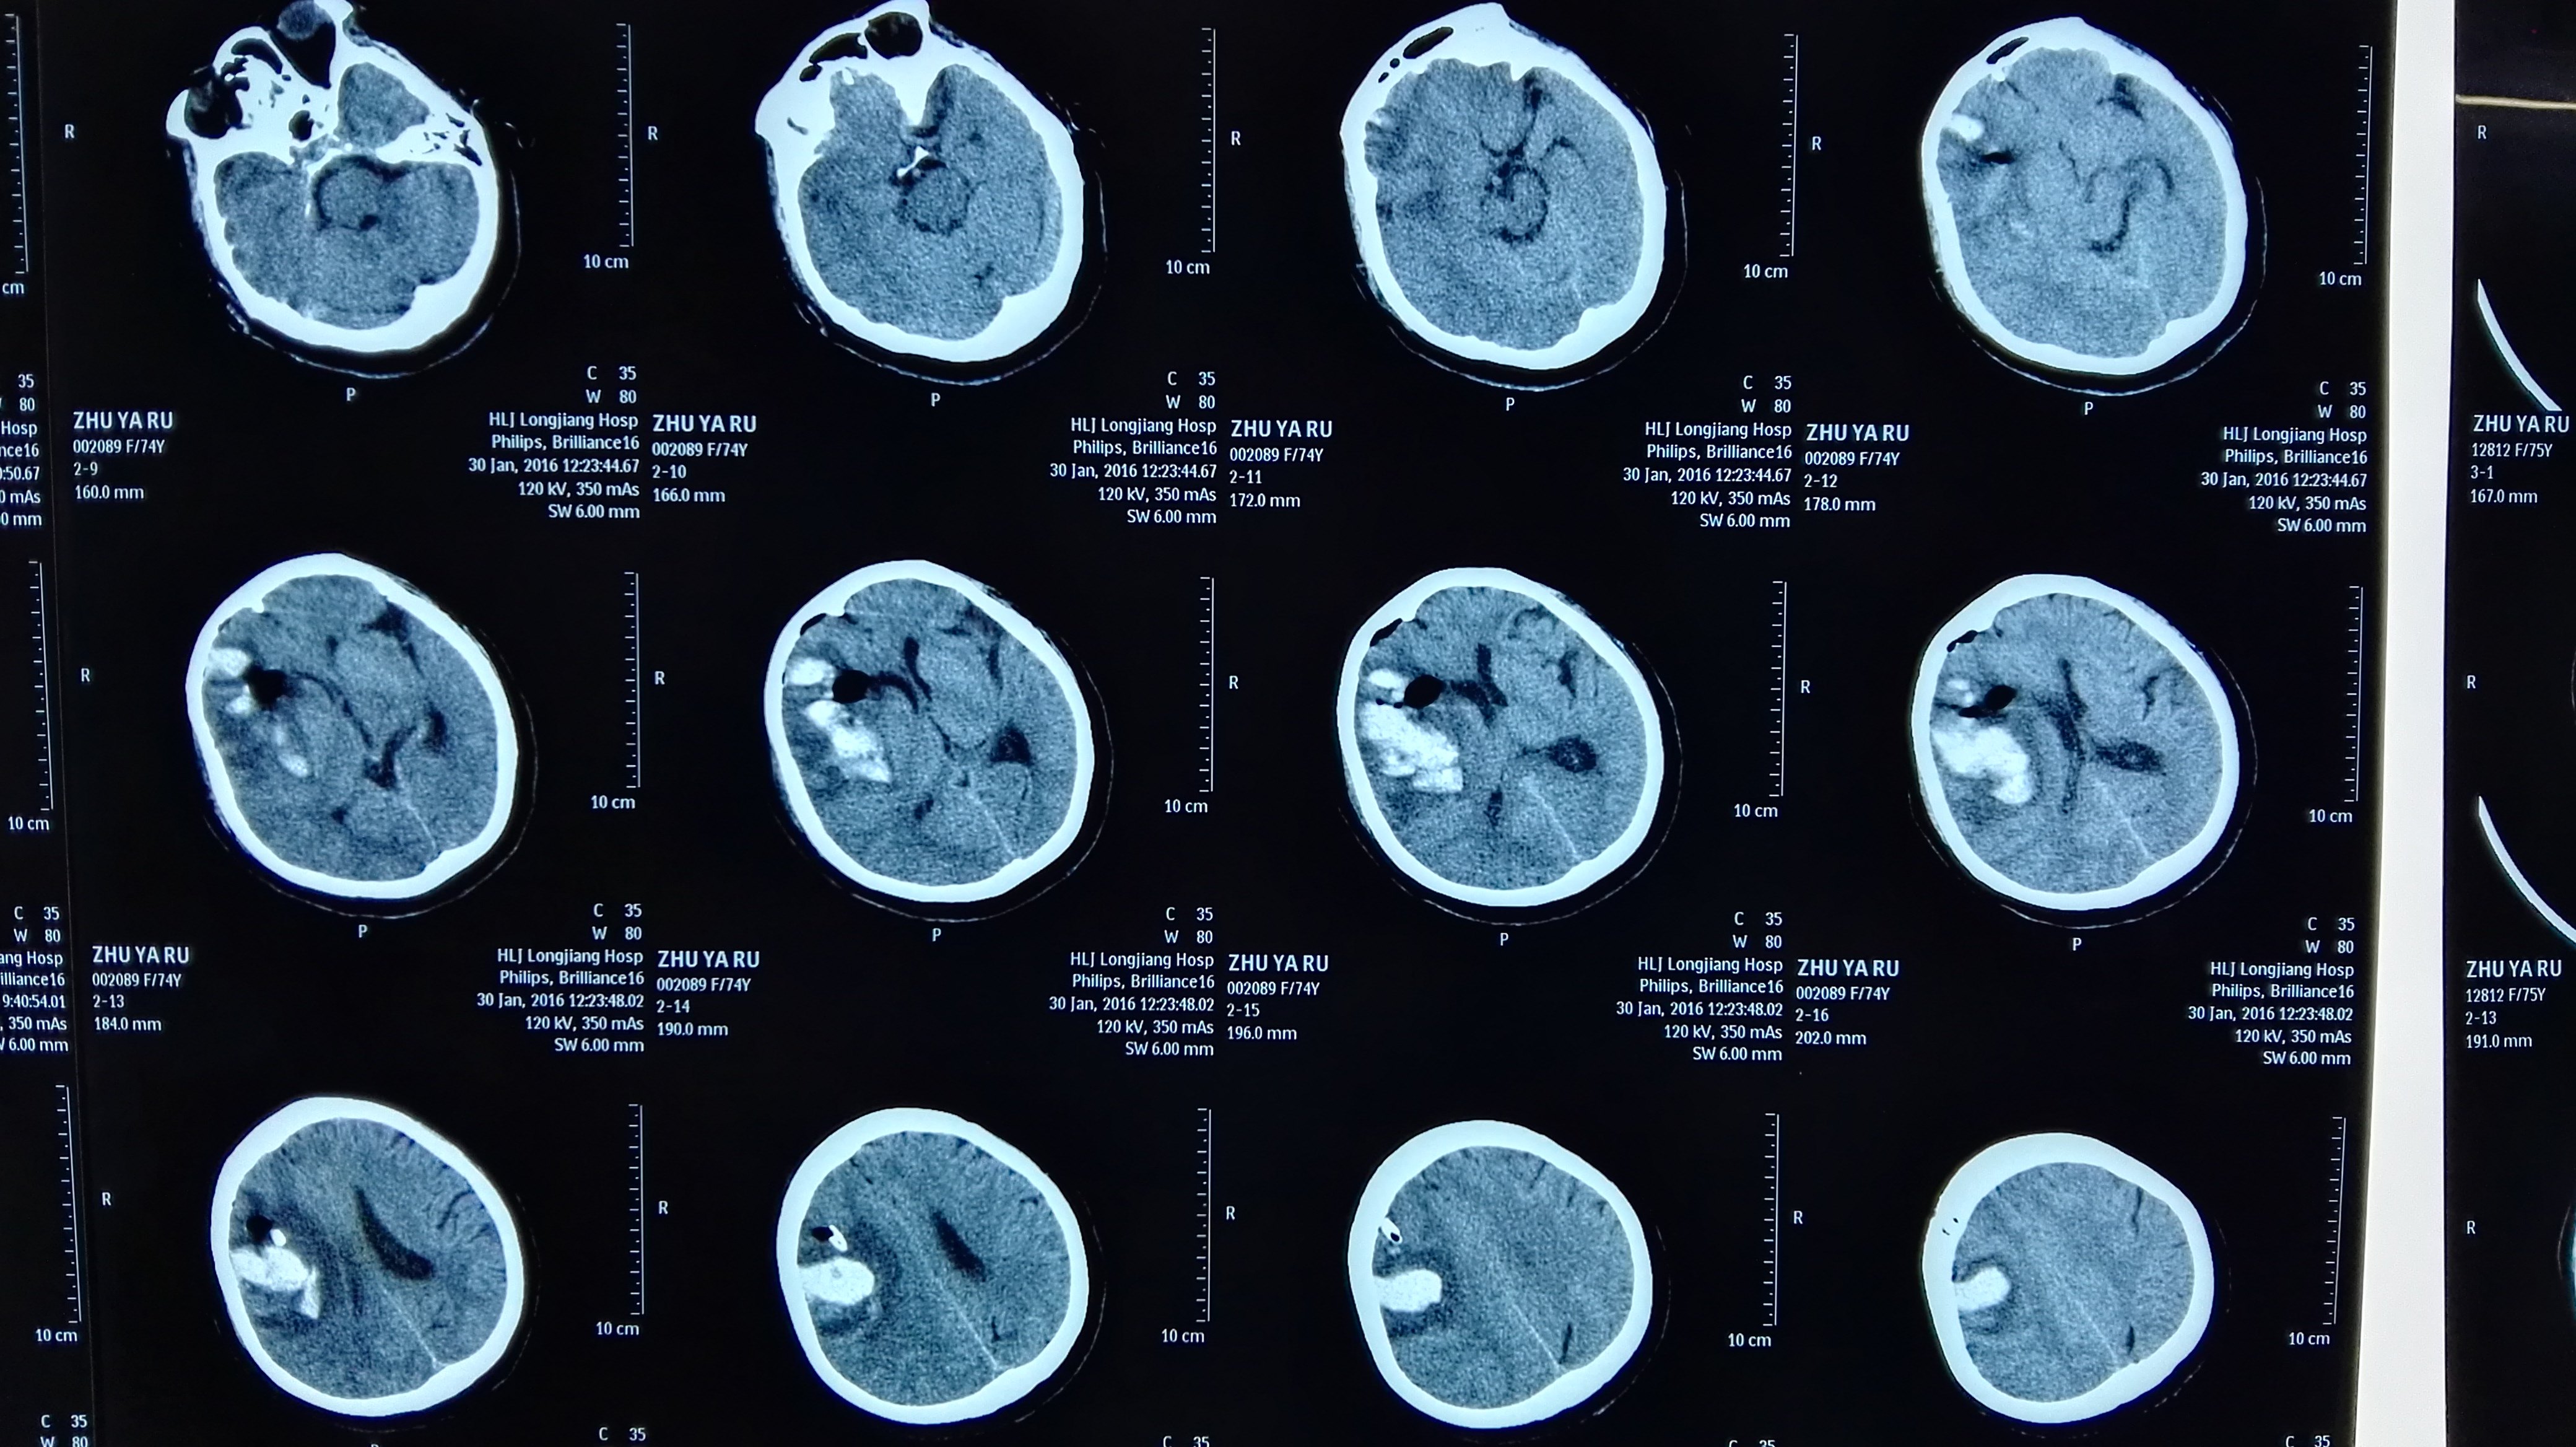

反复多部位脑出血脑淀粉样血管病